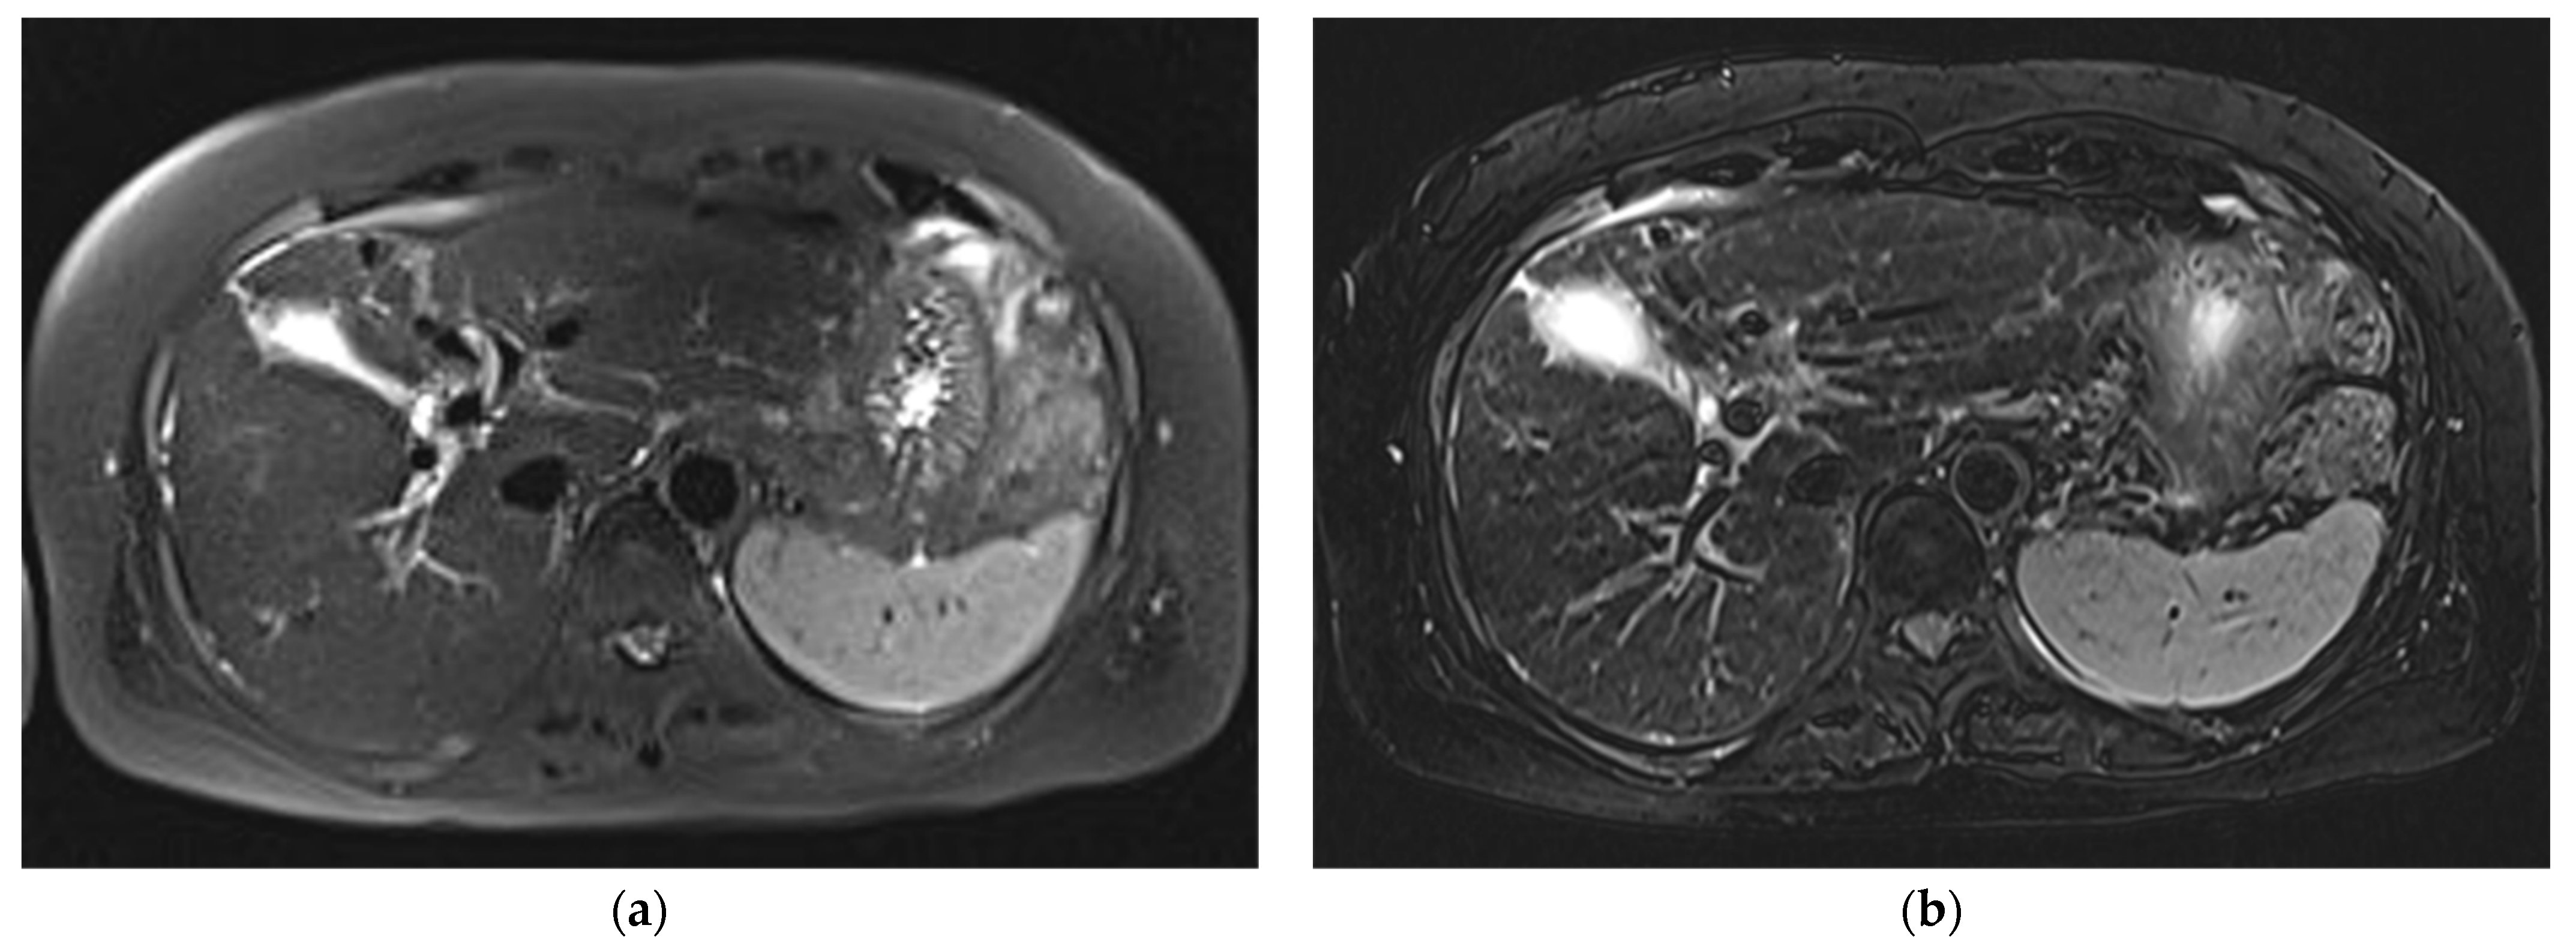

3.1. Subjective Image Quality

3.2. Lesion Assessment